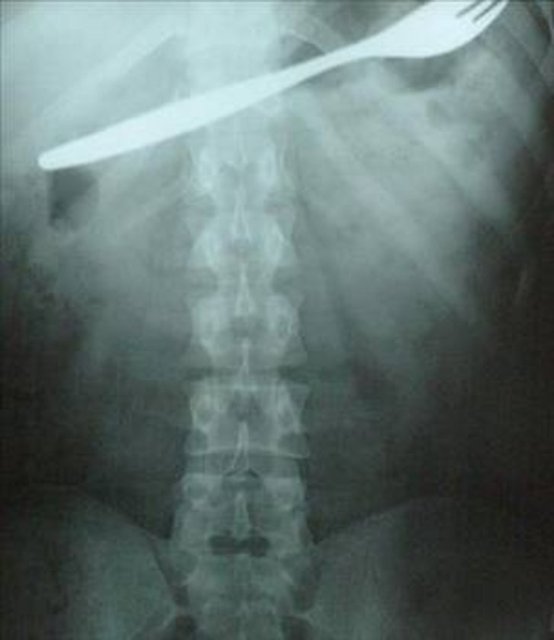

Kahramanmaraş'ın Afşin ilçesinde bir genç kız, karın ağrısı şikayetiyle gittiği hastanede, midesinde çatal olduğunu öğrenince şok oldu. Genç kızın çatalı küçük yaşta yuttuğu sanılırken, çatal başarılı bir ameliyatla çıkarıldı.